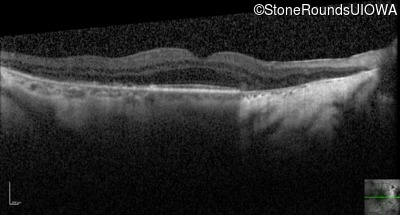

Optical Coherence Tomography - Right - 20/50 -2

Exemplar / OCT Stack